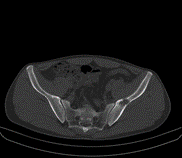

Lezyon; kol ve bacak uzun kemiklerinde, kaburgada, leğen kemiğinde ve kafa-yüz kemiklerinde görülebilir. Monostotik fibröz displazi iskelet sistemi gelişmesi esnasında, poliostotik olanlar ise iskelet sistemi geliştikten sonra ortaya çıkar. Poliostotik olanların %2-3’ü endokrin rahatsızlıklarla birliktedir, ciltte sütlü kahverengi lekelerle birlikte çok kemikte lezyon var ise McCune-Albright sendromu denir. İntramusküler miksoma ile birlikte görülürse Mazabraud Sendromu denir.